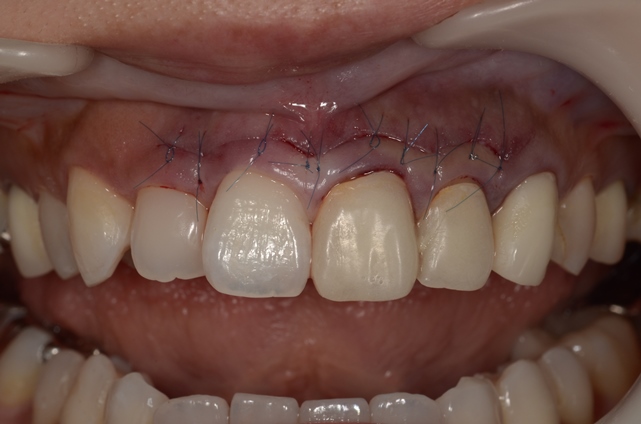

手術直後の縫合時の写真はこちら